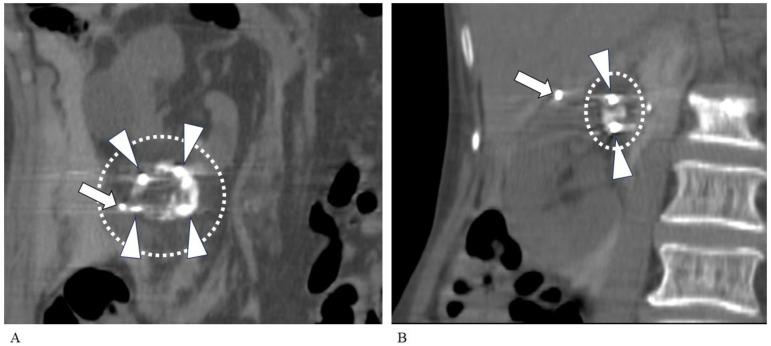

BACKGROUND/OBJECTIVES: Our aim was to compare the complication rates of different embolization materials (absolute ethanol and gelatin sponges) used for combined transarterial embolization (TAE) and to investigate the impact of tumor size on operative time and cryoneedle use during percutaneous cryoablation (PCA).

We treated 27 patients (9 women and 18 men; mean age, 74 years) with 28 early-stage (T1a) renal cell carcinoma (RCC) lesions using combined TAE and PCA between September 2018 and January 2021. During TAE, 15 lesions in 14 patients were embolized using mixed absolute ethanol and iodized oil. The remaining 13 lesions (in 13 patients) were embolized using a gelatin sponge followed by iodized oil. The PCA was performed within 3 to 21 days of the TAE. We compared complications between the TAE subgroups (i.e., absolute ethanol and gelatin sponge) and assessed potential correlations between tumor size and the operative time of the PCA.

All patients were successfully treated by combined TAE-PCA. Local control was achieved for all patients (monitoring period, 1-48 months; median, 28 months). Although the effect of TAE did not differ between subgroups, a significantly higher number of patients in the absolute ethanol group experienced intraprocedural pain than in the gelatin sponge group ( < 0.05). The operative time of the PCA was significantly correlated with the size of the RCC lesion ( < 0.01). The number of cryoneedles used for the PCA was also correlated with the size of the RCC lesion ( < 0.0001).

For TAE prior to PCA for early-stage RCC, gelatin sponges can replace absolute ethanol to reduce intraprocedural pain. Tumor size correlates with operative time and the number of cryoneedles needed for PCA, which suggests the total medical cost for PCA therefore varies based on the tumor's size.